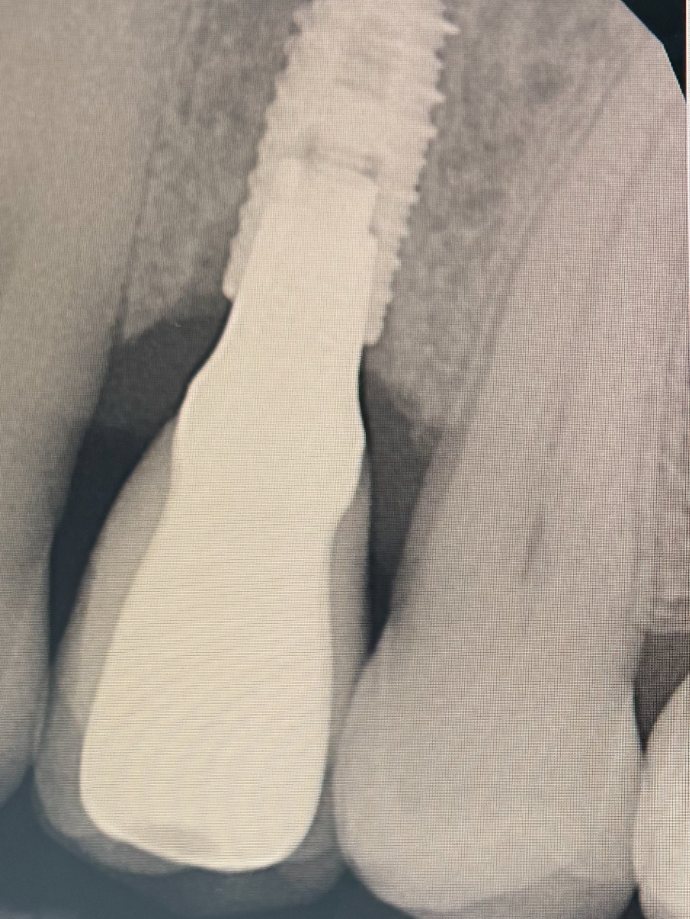

Implantologie dentaire

L‘implant permet de trouver une meilleure qualité de vie tant bien sur le plan esthétique que fonctionnel.

L’implant est une racine artificielle en titane, il est mis en place dans l’os lorsque la racine de la dent est absente à cause d’une agénésie ou d’une ré-infection.

L’implant ne s’appuie pas sur les dents voisines pour remplacer la ou les dents manquantes. L’avantage est de ne pas abîmer les autres dents existantes contrairement aux bridge.

L’implant dentaire permet également de stimuler l’os. En effet l’absence de dent provoque une résorption osseuse rendant difficile tout type de soin par la suite.

L’implant est inséré dans l’os.

Il est ensuite soit laissé sous la gencive, soit recouvert d’une vis de cicatrisation.

Une phase de cicatrisation de 3 à 6 mois est nécessaire : c’est la phase d’ostéointégration, pendant laquelle l’implant s’intègre solidement à l’os.